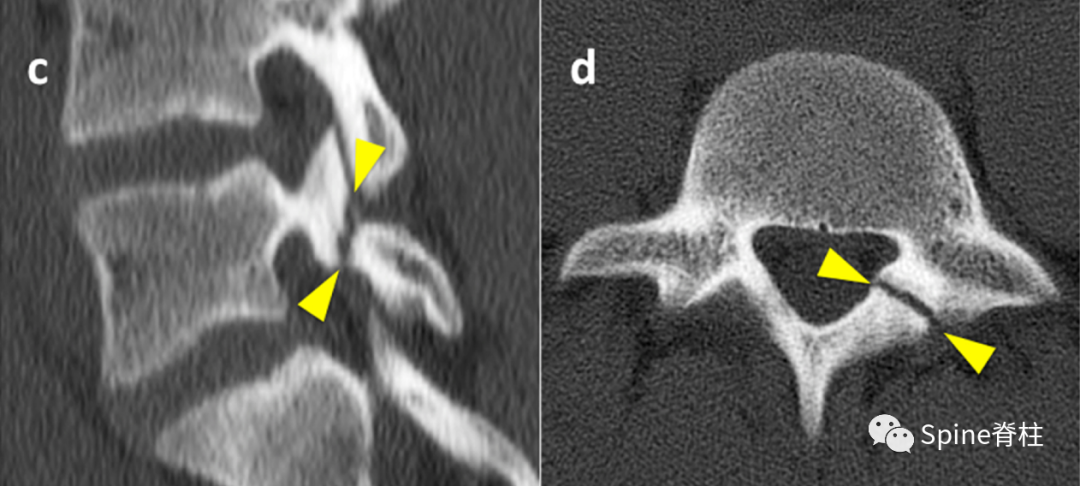

峡部裂的CT分型:A=早期(线性骨折),B=进展期(明显的骨间隙),C=终末期(假关节形成)

右侧为进展期峡部裂,左侧为早期峡部裂,右侧图片是支具固定7个月后愈合

L5椎弓峡部裂典型病例一:男,32岁。A,B: 腰椎正位侧位X线片示无明显椎弓峡部裂征象; C: 腰椎 MRI正中矢状面T1WI示L5棘突基底部与硬膜之间出现脂肪高信号带(箭头示); D: 腰椎CT矢状面重建示L5椎弓峡部骨质不连(箭头示)。

L5椎弓峡部裂典型病例二:男,35岁。A,B: 腰椎正位侧位X线片均无明显椎弓峡部裂征象; C: 腰椎MRI正中矢状面T1WI示L5棘突基底部与硬膜之间出现脂肪高信号带(箭头示); D: 腰椎CT矢状面重建示L5椎弓峡部骨质不连,裂隙较细(箭头示)。

随后,Sairyo教授进一步CT研究,将Morita分型早期又分为最早期(very early): 骨折线模糊或不连续的骨折线和晚早期(late-early): 骨折线清晰明显。

图:腰5双侧峡部裂,右侧为最早期,左侧为晚早期